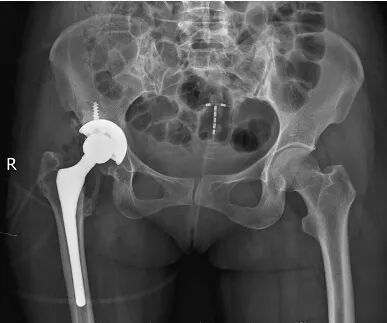

跛行20余年,行全髋关节置换术后丢掉拐杖,回家

髋关节术后需要系统的康复训练,除了活动度的受限和肌力的萎缩,跛行也是很多术后的症状。很多跛行会造成长

病情描述(发病时间、主要症状、症状变化等):髋关节置换术后走路是否跛行曾经治疗情况和效果:没怎么治疗

[运动美学]髋关节术后跛行 拉伸康复[运动美学]髋关节术后跛行 拉伸康复

40年的跛行,屈辱无奈。术后5天即可行走,他对郴州市第一人民医院骨科二区的王朝晖博士、唐艳平医生充满了

先天性髋脱位术后跛行原因及预防,张立军,吉士俊,刘卫东,中华骨科杂志杂志。先天性髋脱位治疗后关节功能的